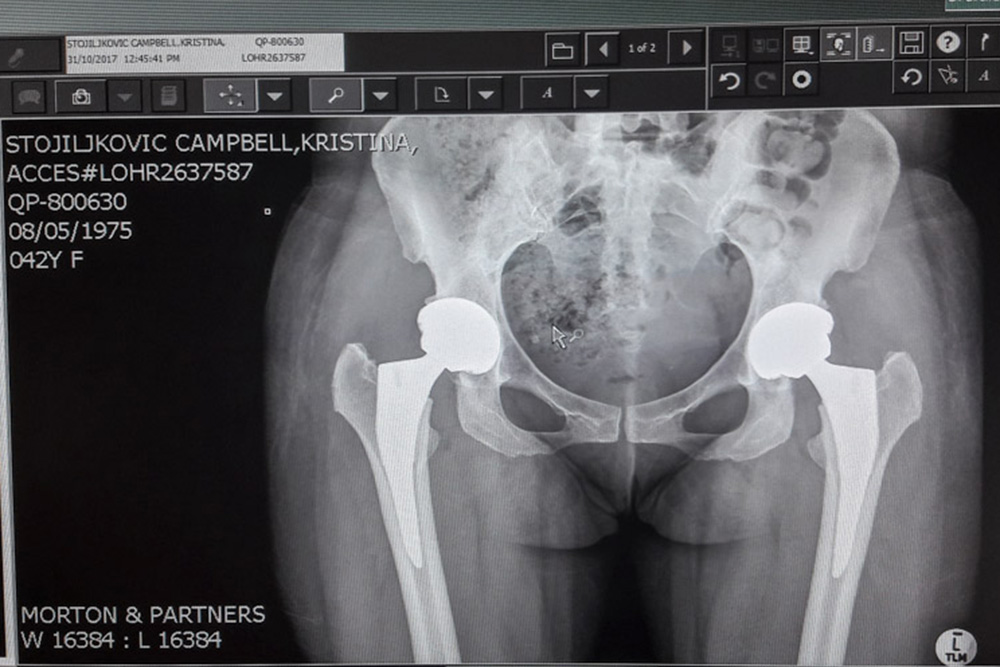

Its been a 14 year journey for me to get to this final chapter and to Mag’s door. My story leads to a total bilateral hip replacement surgery four years ago, a year of learning to walk, one Psoas release surgery and another year of recovery. As a result I have scars on my hips, memories of physical and emotional struggles and one side that will never be fully recovered. Today I am happy to have my mobility back and to be able to experience life to its fullest again with my four year old daughter and husband that have supported me through it all.